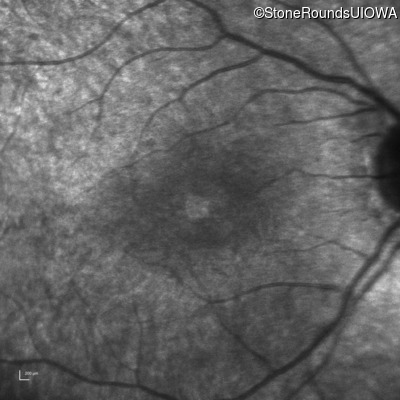

Infrared Fundus Photograph - Right - 20/25 -2

Exemplar

Infrared Fundus Photograph - Left - 20/32